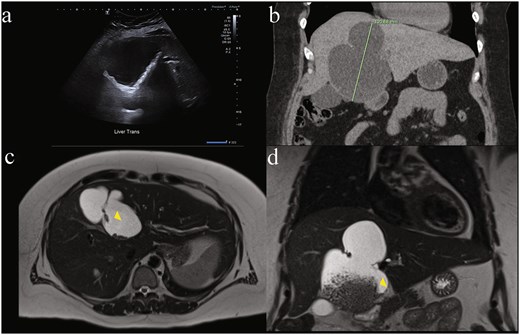

Ultrasound measured a 13 × 17 × 9.5 cm complex cystic lesion in segment IVb of the liver, exhibiting thick septations, wall calcifications with internal matrix echogenicity or debris, without common bile duct (CBD) dilatation (5.3 mm) (Fig. 1a). Subsequent computed tomography (CT) characterized the lesion as a large (9.8 × 6.8 × 12.1 cm) non-enhancing cyst occupying segments IV a/b with internal debris, peripheral calcifications and left hepatic lobe biliary tree dilatation concerning for biliary cystadenoma (Fig. 1b). Magnetic resonance (MR) demonstrated dependent debris with characteristic "hydatid sand" appearance and septations (Fig. 1c and d), without biliary involvement or dilatation. Despite negative hydatid serologies, WHO CE1 and CE2 active stage classification according to WHO informal working groups on Echinococcosis guidelines (constructed for ultrasound) was suggested. Consequently, preoperative albendazole 400 mg twice daily was commenced on the advice of the infectious disease specialists. Tumour markers Alpha-fetoprotein (AFP) and Carcinoembryonic antigen (CEA) were not elevated. Ca 19–9 was not tested.

Diagnostic difficulty represented in single patient imaging series of mucinous cystic neoplasm of the liver (MCN-L). There is wide variation between modalities in same patient: (a) ultrasound of liver demonstrating internal matrix echogenicity or debris, (b) coronal contrast enhanced CT showing non-enhancing cystic lesion 12.1 cm in largest dimension occupying most of segment IV a and b with internal debris, peripheral calcifications and left hepatic lobe biliary tree dilatation reported as concerning for biliary cystadenoma, and magnetic resonance imaging (MRI) T2-weighted. (c) Axial and (d) coronal views showing dependent debris with characteristic ‘hydatid sand’ (yellow arrowhead) appearance and septations concerning for hydatid disease that were later found to be bile stones.